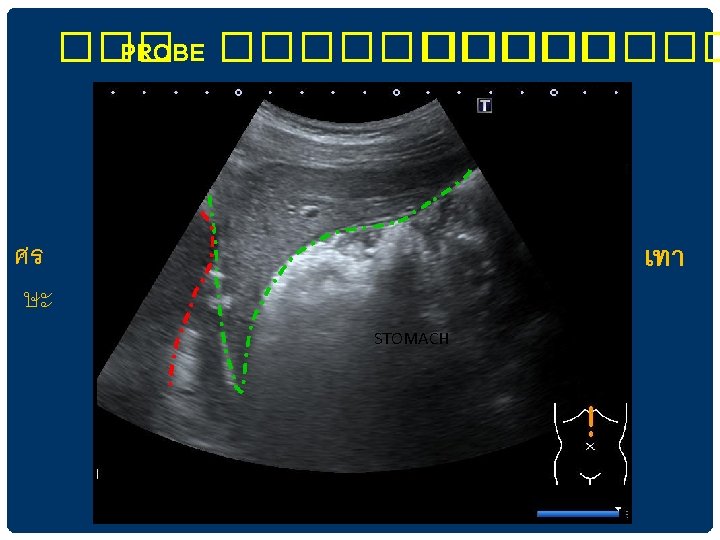

RIGHT SUBCOSTAL SECTION IN LEFT LATERAL DECUBITUS POSITION ��������� lesion ����������